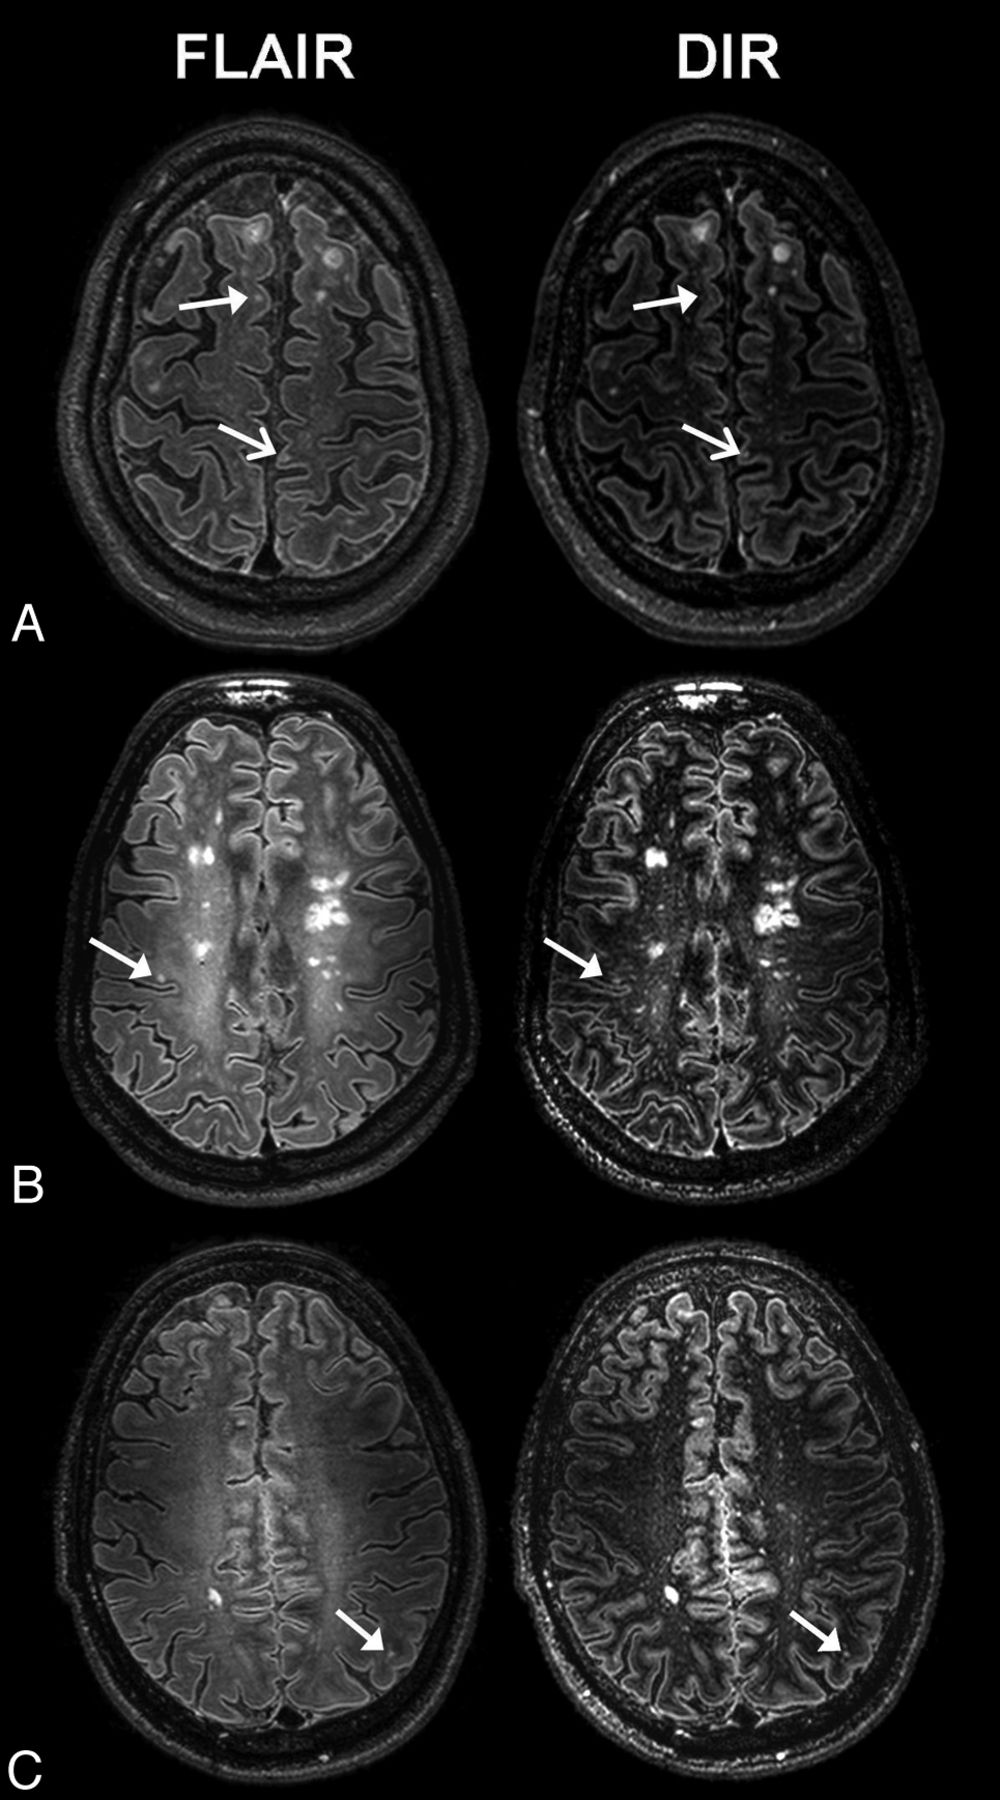

As opposed to 1.5T and 3T, the highest total cortical GM lesion detection at 7T was found by the 3D-FLAIR sequence. To investigate this finding further, we reviewed a subset of patients and compared 3D-FLAIR and 3D-DIR sequences side by side (Fig 3). This comparison suggested several possible explanations involving the design of both sequences as well as our rating process. First, the design of sequences on our 7T system causes a multiple-layered appearance of the cortex, which differs between 3D-DIR and 3D-FLAIR22 and has recently been described as differing among anatomic regions in the brain.39 The cortex is often relatively more hyperintense on 3D-DIR than on 3D-FLAIR because of the attenuation of WM at DIR (Fig 3). This might have caused diminished visibility of cortical lesions on 3D-DIR. Furthermore, due to the combination of 2 inversion pulses at 3D-DIR, besides CSF and WM, additional tissue components are also partly attenuated, including lesions and particularly the periphery of a lesion. This did not make small lesions completely invisible but often too inconspicuous to score, a phenomenon that has also been described at lower field strengths.15 Because T1 values are field-strength-dependent, this effect could be different at a high field and should be further investigated. In addition to these aspects, the resolution of 3D-FLAIR was better than that of 3D-DIR, 0.51 mm3 versus 0.64 mm3 voxel volumes respectively, which might affect the ability to detect small lesions.

Examples of scoring differences at 7T MR imaging: 3D-FLAIR versus 3D-DIR, found while reviewing a subset of images retrospectively. A, A juxtacortical lesion (closed arrows) that was scored on 3D-FLAIR but not on 3D-DIR because of differences in contrast between the lesion and the cortical gray matter. On 3D-DIR, the cortex looks relatively hyperintense compared with 3D-FLAIR because of the attenuation of white matter, which might have hindered lesion detection. The open arrows show a juxtacortical lesion that was detected at both sequences. B, The closed arrows show a mixed lesion that was scored on 3D-FLAIR but not on 3D-DIR because of conservative scoring/distraction by many small hyperintensities and its smaller size on 3D-DIR. C, A juxtacortical lesion that was scored on 3D-FLAIR but not on 3D-DIR images (closed arrows) because tissue was attenuated too much by using the DIR sequence, which decreases the size of the lesion.

Second, the scoring process might also have hampered lesion detection at 3D-DIR. There is an abundance of small signal abnormalities, mostly perivascular spaces, on 3D-DIR (Fig 1). This may have caused too much distraction while scoring lesions so that they were overlooked or not specified as being a lesion. Furthermore, we used a rather conservative scoring system: Focal hyperintensities were only specified as lesions if they were in line with the consensus guidelines for scoring of cortical lesions on DIR, which were developed by the MAGNIMS study group.25 Hyperintensities or inhomogeneities in the cortex were interpreted as artifacts or as small vessels more easily on the 3D-DIR sequence than on the 3D-FLAIR sequence, which may have caused an under-representation of lesions at 3D-DIR.